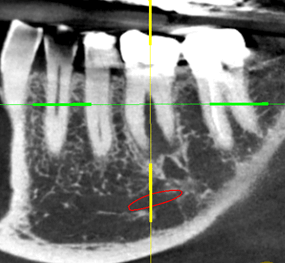

This patient had a crowned first molar tooth with area of infection (the dark area between the roots) (A). This tooth was removed, and dental implant (titanium screw) was placed immediately follow the extraction. Three month later, the restorative specialist placed a crown attached to the implant (B).

A